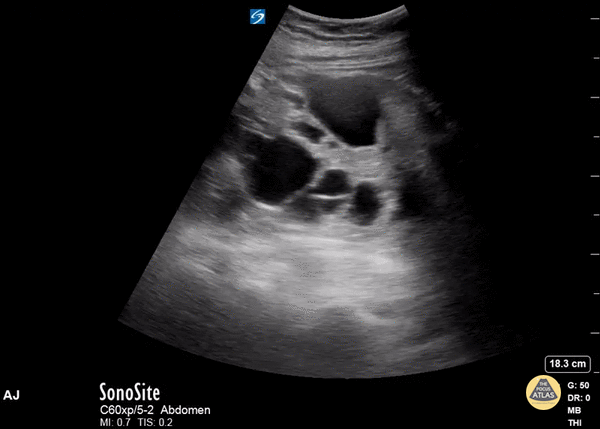

This middle-aged adult female presented to the emergency department with abdominal pain. The patient reported history of polycystic kidney disease. Bedside renal ultrasound revealed multiple renal cysts in both the cortex and medullary areas of the kidney, consistent with her history. Stones and hydronephrosis would be difficult to detect in the setting of polycystic kidney disease. Ahmad Jaber, MBBS PGY3 Resident Physician, Central Michigan University Emergency Medicine Residency